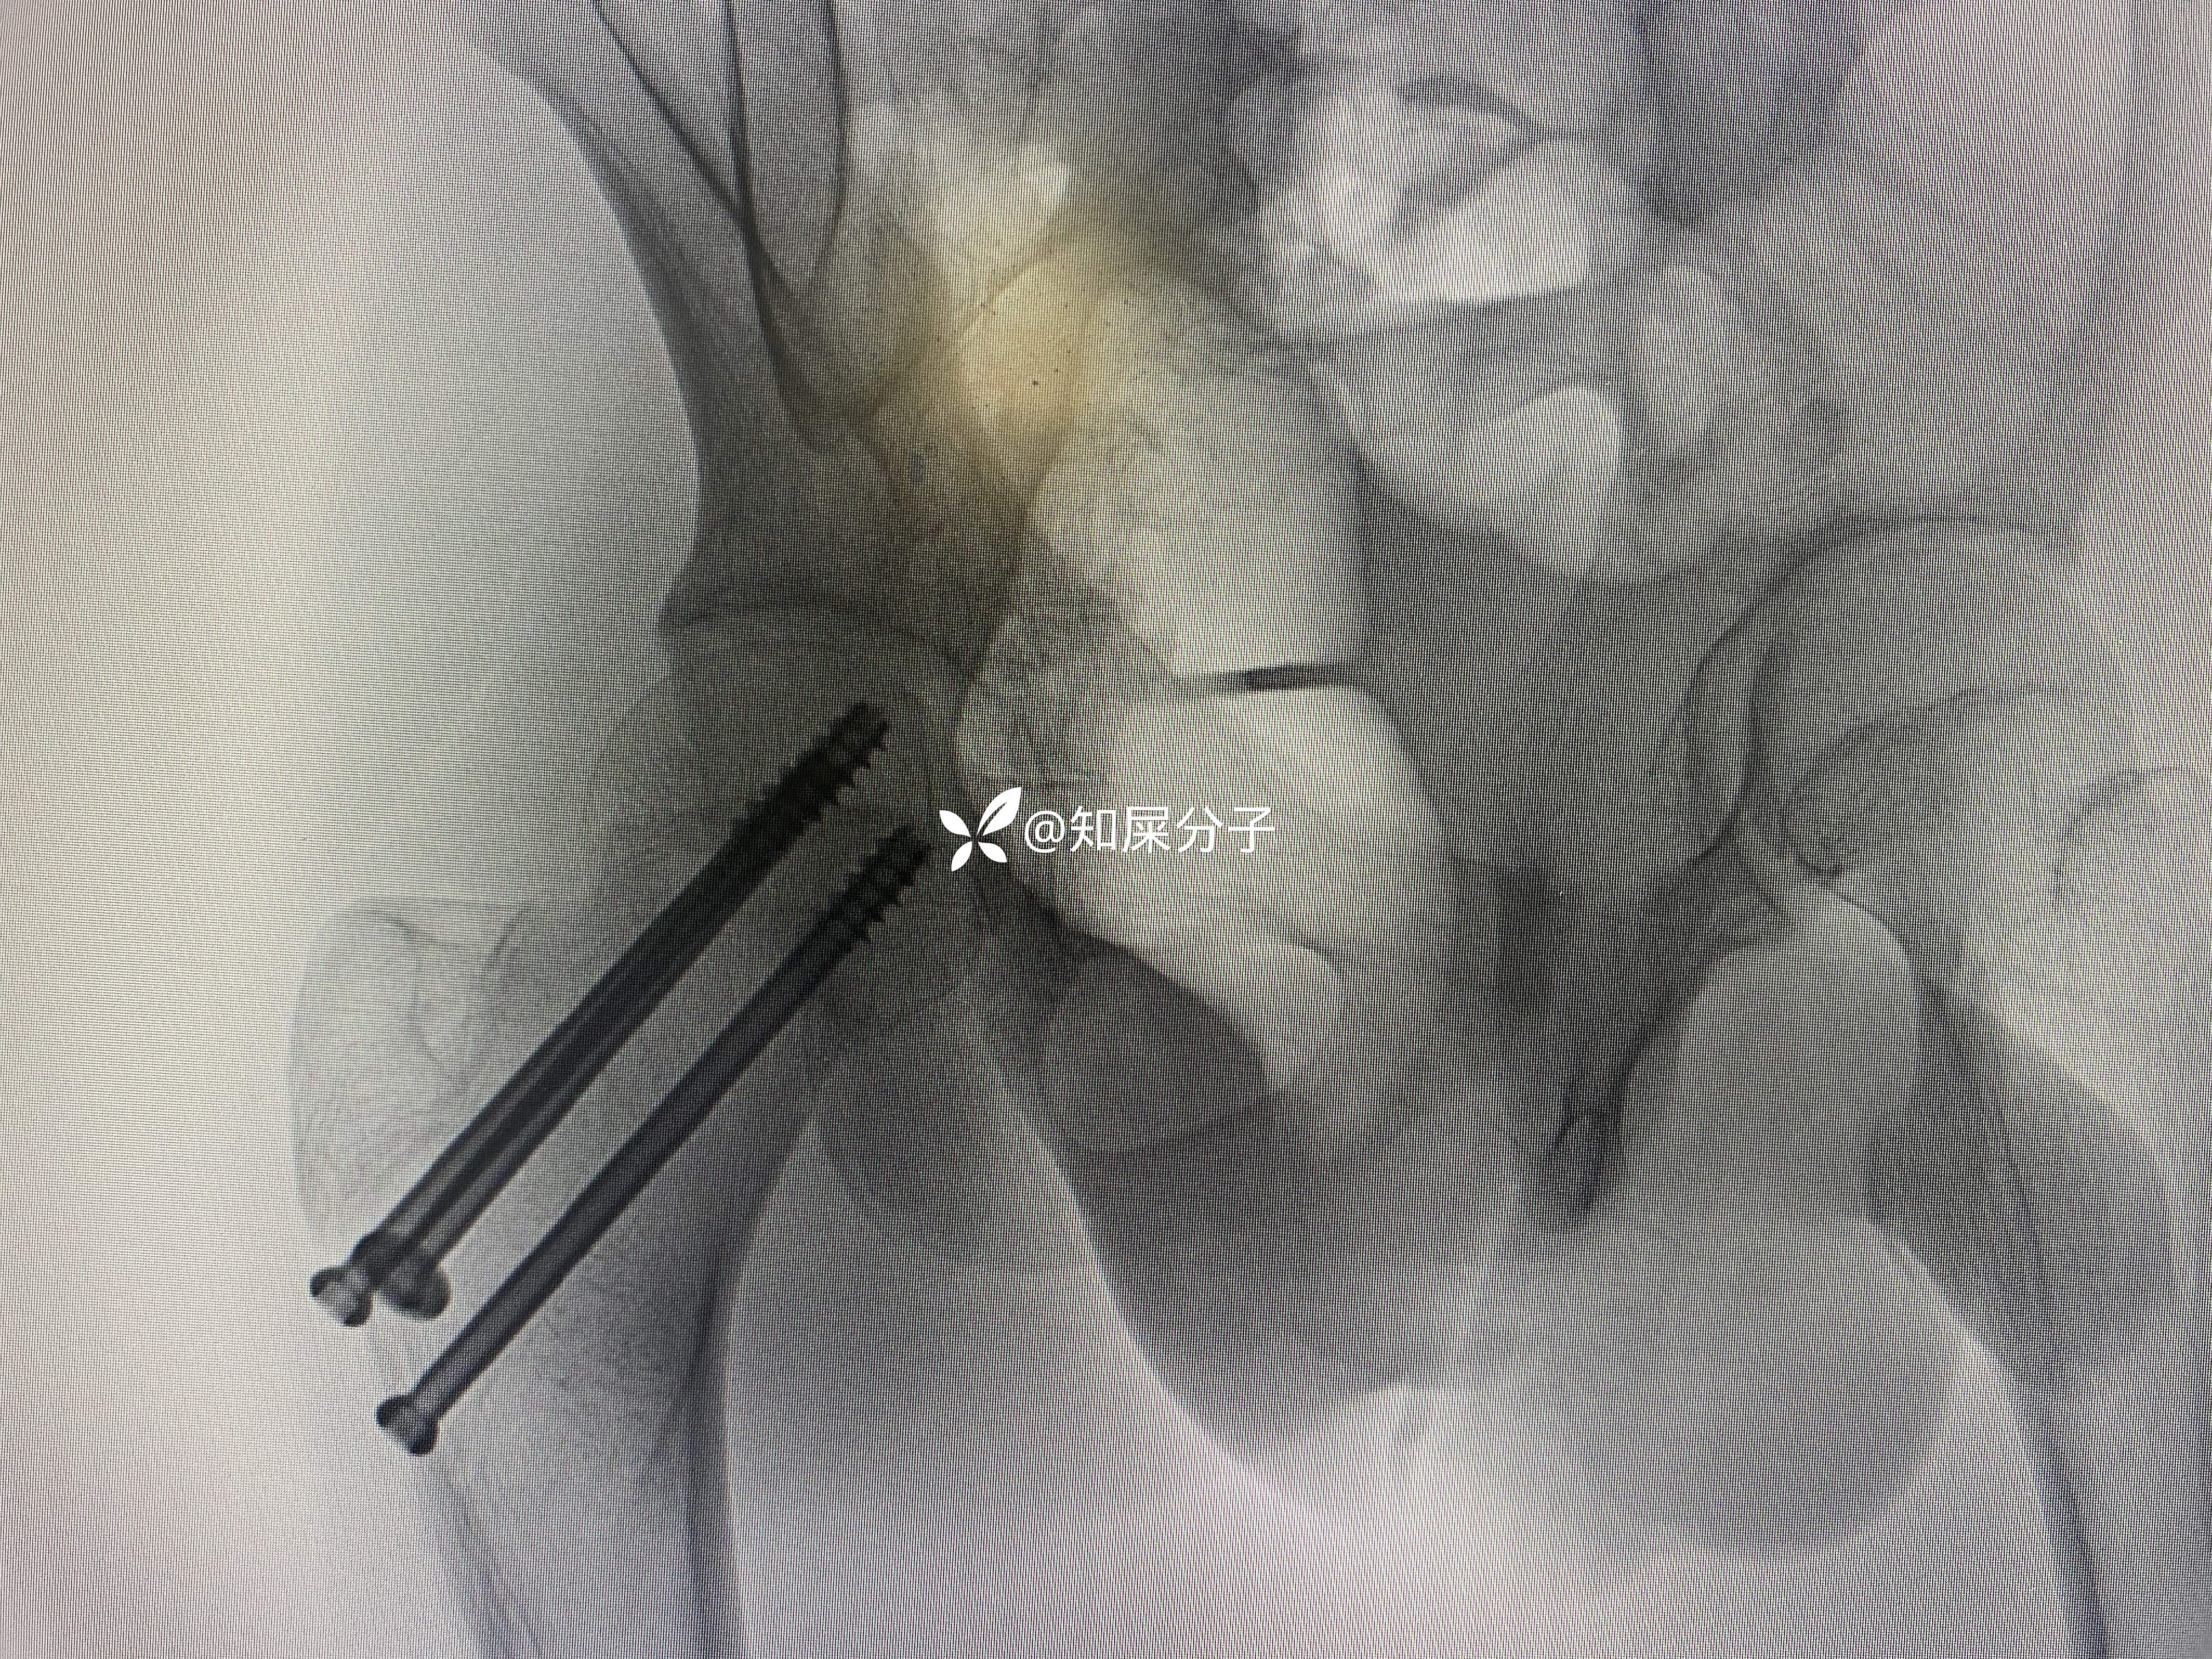

入院后完善检查24小时内完成手术

术后如下

17岁

你是按儿童的做

按儿童的做几根钉

如何布局螺钉

还是按成人的做?